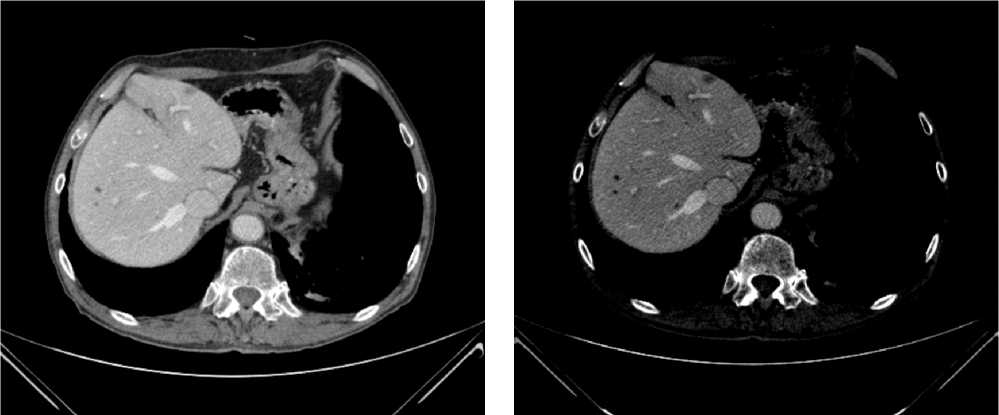

Выполнена компьютерная томография (КТ) органов грудной клетки, брюшной полости в июле 2019 г. Инфильтративных изменений в легких не обнаружено. Выявлено новообразование антрального отдела, малой кривизны и передней стенки желудка, распространяющееся на заднюю стенку, преимущественно на препилорический отдел. Имелись признаки локального перехода образования на большой сальник, гепатодуоденальную связку с периваскулярным ростом и признаками лимфоваскулярной инвазии. Многочисленные забрюшинные ЛУ сливались между собой в конгломераты размерами до 40 × 29 мм с частичным вовлечением почечных артерий. Также билобарно обнаружены немногочисленные очаговые образования в печени до 10 мм. Высказано подозрение на перитонеальный канцероматоз (рис. 3).

Рис. 3. Результаты компьютерной томографии органов брюшной полости у пациента 80 лет с диагнозом метастатический рак желудка с признаками микросателлитной нестабильности (июль 2019 г., до лечения)

Fig. 3. Results of a CT scan of the abdomen in an 80-year-old patient with metastatic MSI-H gastric cancer (July 2019, before treatment)

В результате обследования был установлен диагноз рака антрального отдела желудка (c)T4аN3вM1. По решению онкологического консилиума, учитывающего молекулярно-генетический профиль опухоли, а также возраст пациента, выраженность сопутствующей патологии (в анамнезе острое нарушение мозгового кровообращения (ОНМК), острый инфаркт миокарда (ОИМ), фибрилляция предсердий (ФП), постоянная форма), ограничивающей проведение ПХТ, была начата ИТ 1 линии пембролизумабом. С сентября 2019 г. по декабрь 2021 г. проведено 29 циклов ИТ 1 линии по схеме пембролизумаб в монорежиме с максимальным эффектом частичный регресс (рис. 4). Осложнений лечения не зарегистрировано.

Рис. 4. Частичный регресс по данным компьютерной томографии органов брюшной полости на фоне иммунотерапии пембролизумабом у пациента 81 года с диагнозом метастатический рак желудка с признаками микросателлитной нестабильности (декабрь 2021 г.; выживаемость без прогрессирования составила 25+ мес.)

Fig. 4. Partial response according to abdominal CT scan during immunotherapy with pembrolizumab in an 81-year-old patient diagnosed with MSI-H metastatic gastric cancer (December 2021; progression-free survival was 25+ months)